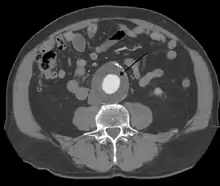

CT reconstruction image of an abdominal aortic aneurysm

A 6.5 cm AAA with a 3 cm lumen